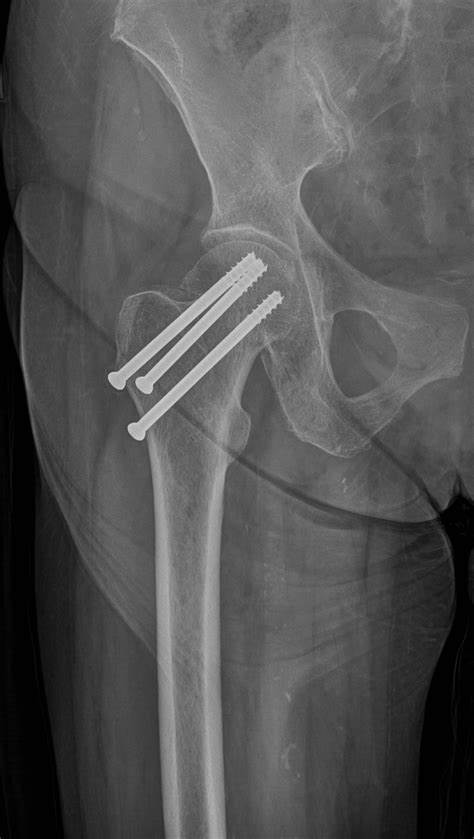

What internal fixation method has been used to internally fix this hip?

Cannulated nail screws